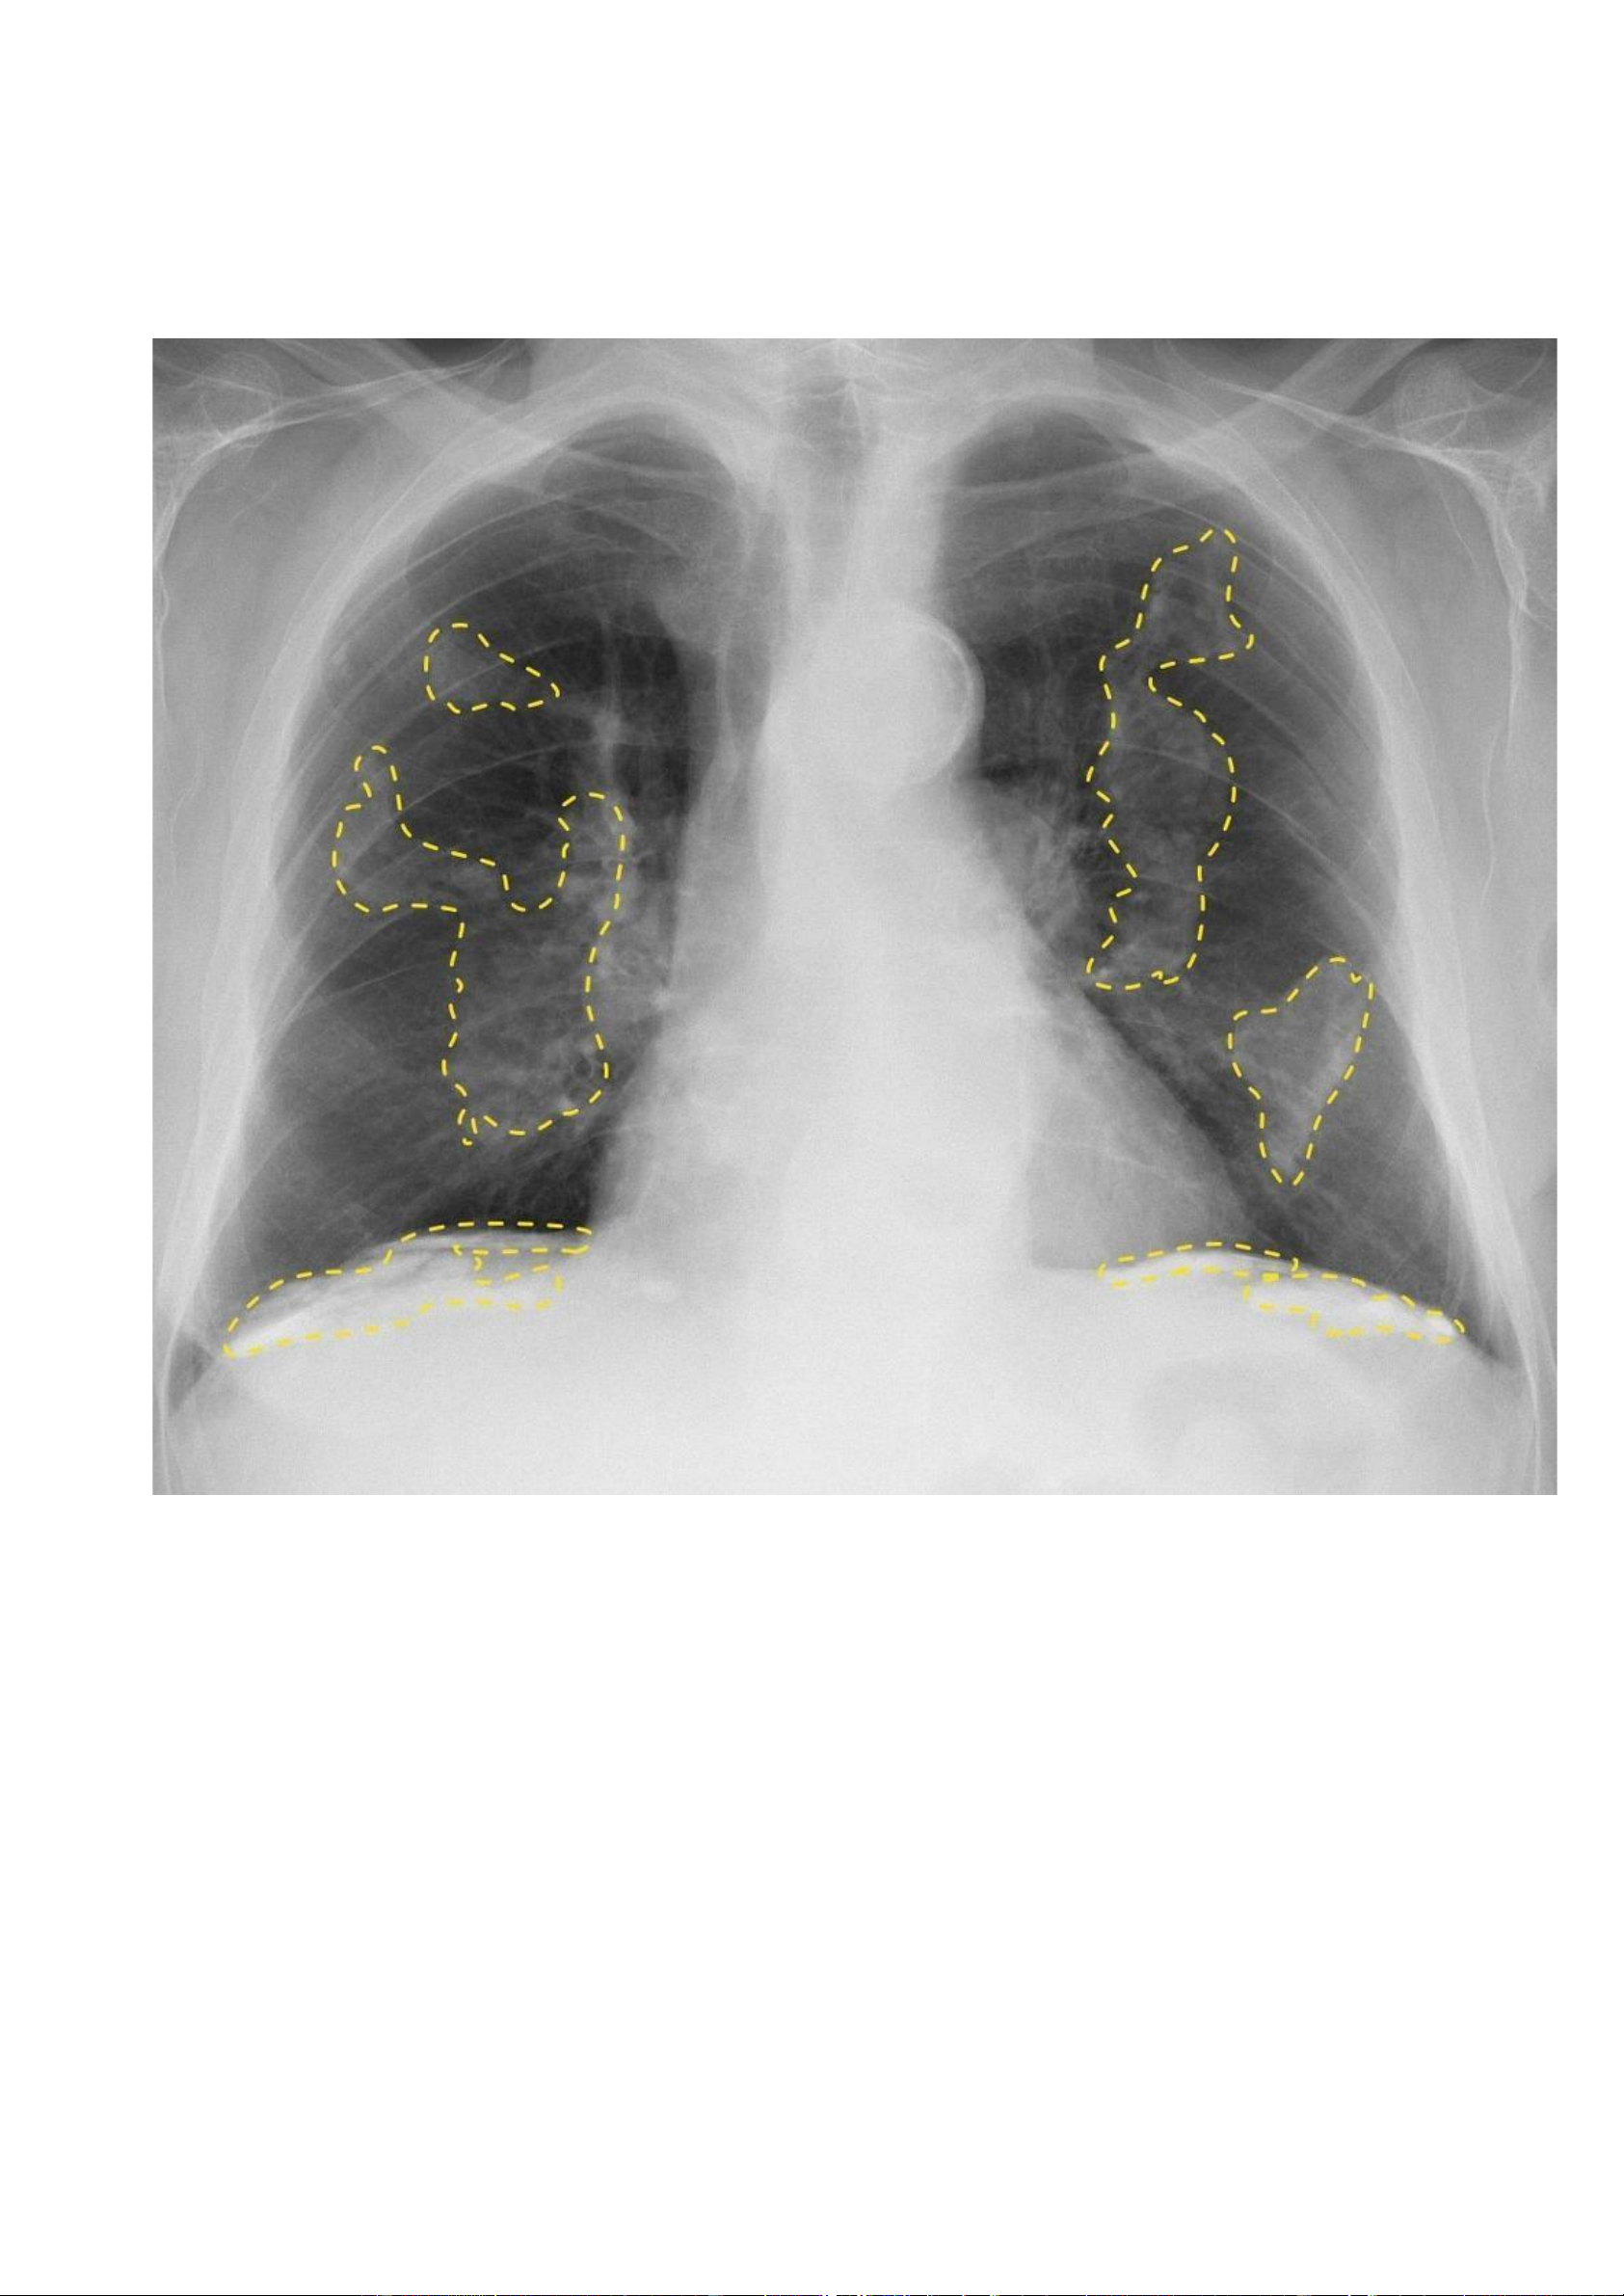

Nguồ https://radiopaedia.org/cases/pleural-plaques -

nh nhân: Bệnh nhân nam, 65 tuổi, khó thở và ho có đờm. - Hình ả lOMoAR cPSD| 22014077 Phan Tùng Bách

Vôi hoá màng phổi hai bên dạng bản đồ, bao gồm cả bề mặt nửa cơ hoành hai bên. lOMoAR cPSD| 22014077 Phan Tùng Bách ờng hợ n link: Thông tin bệ nh X quang:

Các mảng màng phổi vôi hoá (các đường nét đứt màu vàng). 7.5. Trư p 5: lOMoAR cPSD| 22014077 Phan Tùng Bách -